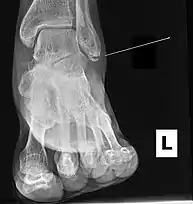

Radiograph showing a Maisonneuve fracture of the proximal fibula

The Maisonneuve fracture is a spiral fracture of the proximal third of the fibula associated with a tear of the distal tibiofibular syndesmosis and the interosseous membrane. There is an associated fracture of the medial malleolus or rupture of the deep deltoid ligament of the ankle. This type of injury can be difficult to detect.[1][2]

Fracture of the medial malleolus seen on X-ray scan (left ankle)